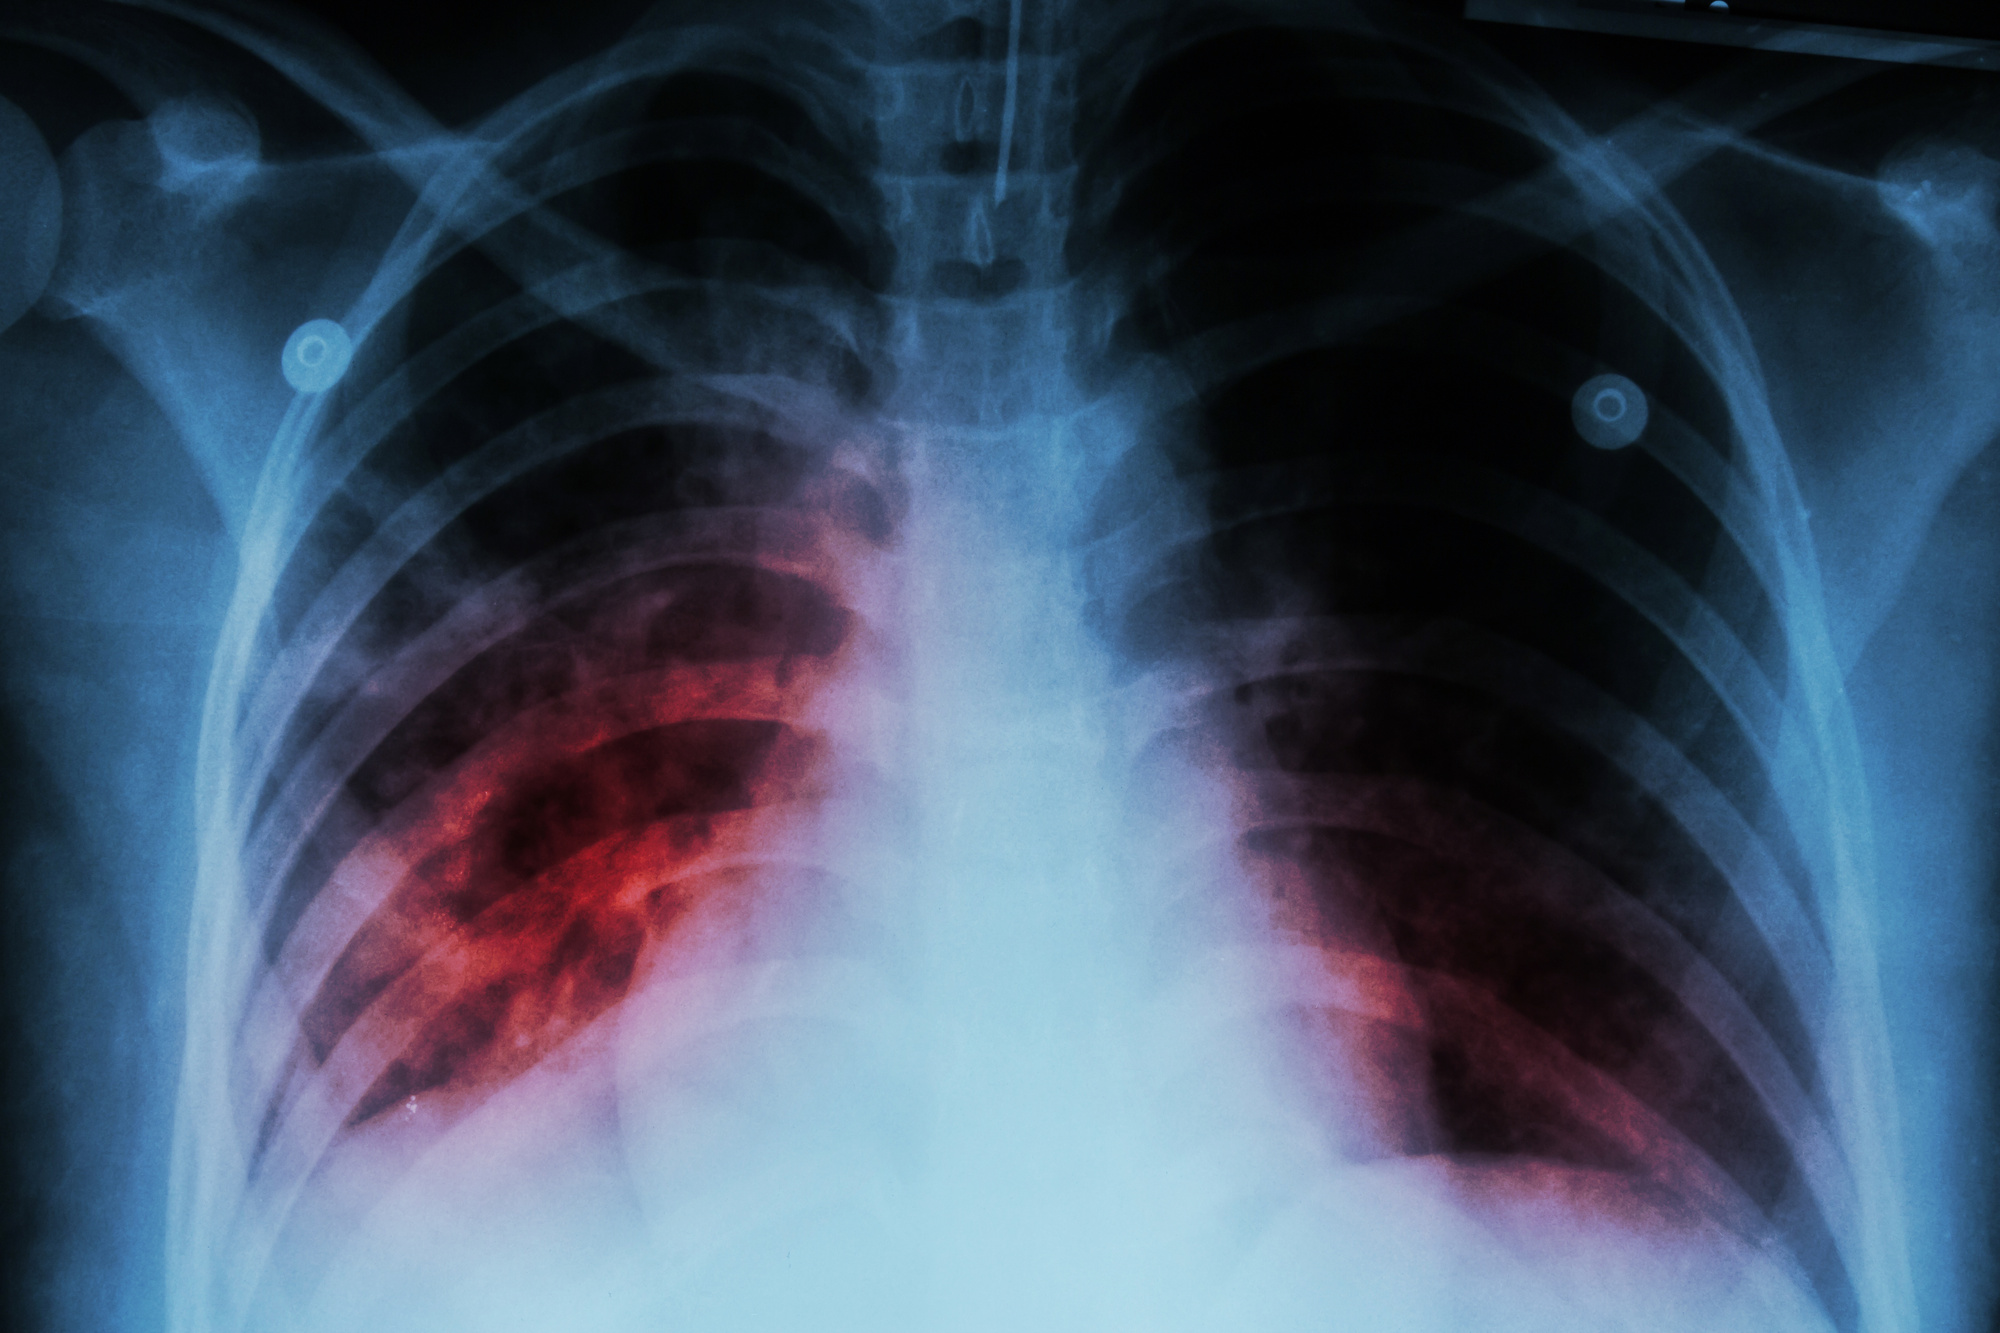

How Many Types Of Tb In Human Body . When tuberculosis (tb) germs survive and multiply in the lungs, it is called a tb infection. Not everyone infected with tb bacteria becomes sick. Tuberculosis and seven very closely related mycobacterial species (m. Mungi) comprise what is known as the. Every year, 10 million people fall ill with tuberculosis (tb). In 2022, an estimated 10.6 million people fell ill with tuberculosis (tb) worldwide, including 5.8 million men, 3.5 million women and 1.3 million children. Despite being a preventable and curable disease, 1.5 million. A person needs to inhale only a few germs to become infected. Latent tb infection (also called inactive tb) and tb disease. A tb infection may be in one of three stages. Tb is present in all countries and age. Tuberculosis (tb) does not only affect the lungs — it can also affect other areas of the body, known as extrapulmonary tb.